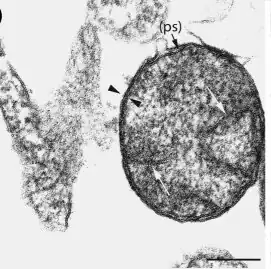

.jpg)